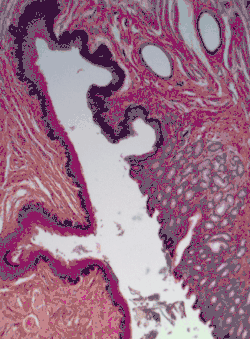

A stratified squamous epithelium consists of squamous (flattened) epithelial cells arranged in layers upon a basal membrane. Only one layer is in contact with the basement membrane; the other layers adhere to one another to maintain structural integrity. Although this epithelium is referred to as squamous, many cells within the layers may not be flattened; this is due to the convention of naming epithelia according to the cell type at the surface. In the deeper layers, the cells may be columnar or cuboidal.[1] There are no intercellular spaces. This type of epithelium is well suited to areas in the body subject to constant abrasion, as the thickest layers can be sequentially sloughed off and replaced before the basement membrane is exposed. It forms the outermost layer of the skin and the inner lining of the mouth, esophagus and vagina.[2]

In the epidermis of skin in mammals, reptiles, and birds, the layer of keratin in the outer layer of the stratified squamous epithelial surface is named the stratum corneum. Stratum corneum is made up of squamous cells which are keratinized and dead. These are shed periodically.

- [Micrograph] of normal stratified squamous epithelium and the metaplasic epithelium of Barrett's esophagus (left of image). Alcian blue stain.

- Non-keratinized stratified squamous epithelium, image highlights the epithelial nucleuses, rest of the epithelial layer, underlying connective tissue and other epithelia